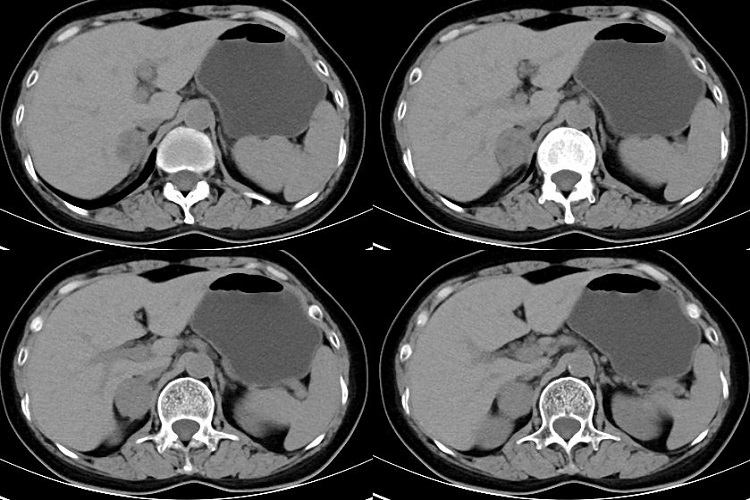

肾上腺位于肾筋膜囊内,周围有丰富的低密度脂肪组织,因而正常肾上腺能够清楚显示。平扫检查,正常肾上腺呈软组织密度,类似肾脏实质,不能分辨皮、髓质。肾上腺的形态因人而异,即使同一肾上腺在不同层面上也表现各异右侧肾上腺常呈斜线状、倒“V”或倒“Y”形。左侧者多为倒“V”、倒“Y”

形或三角状。肾上腺边缘多平直,也可轻度一致性外突或内凹,表面光滑,无外突结节。